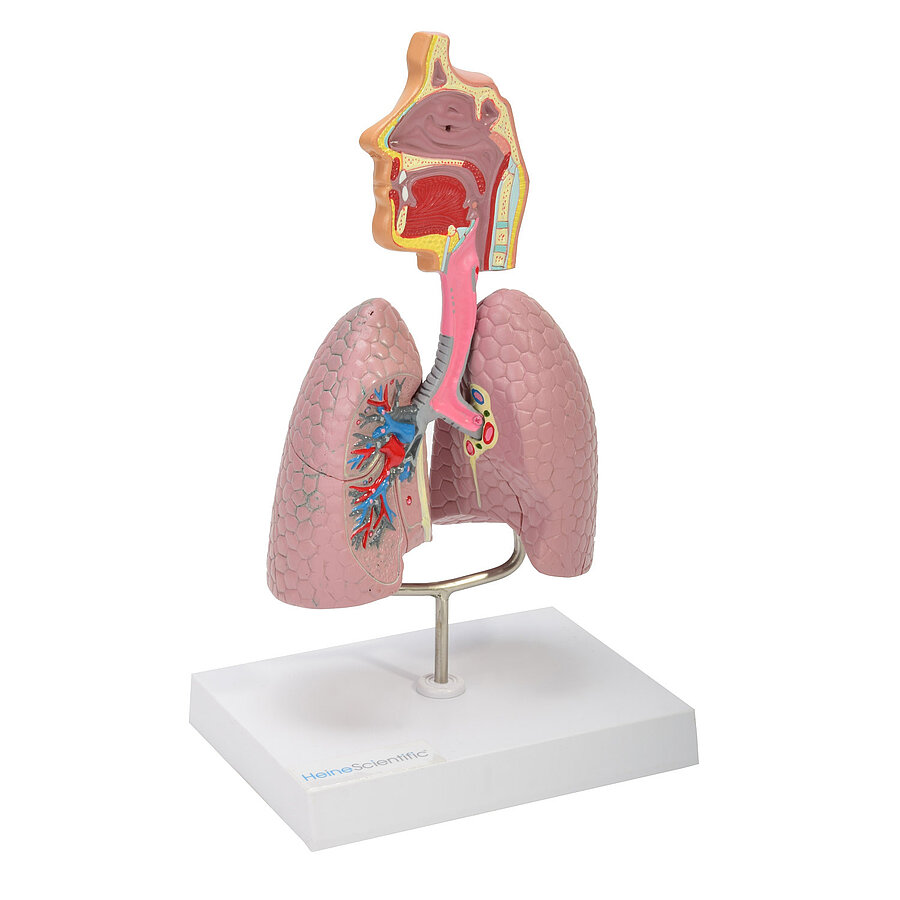

Atemwegsmodell

Präzise Nachbildung der Atemwege des Menschen

Perfekt für die Patientenaufklärung und das Medizinstudium

Auf einem Kunststoff-Sockel montiert, abnehmbar

Aufwändige Kolorierung

Maße: 27 x 16,5 x 12 cm (H x B x T)

Detaillierte Modelle für medizinische Ausbildungen

In unserem Sortiment finden Sie zahlreiche Modelle von HeineScientific sowohl für die Humanmedizin als auch für den Veterinärbereich. Hierzu zählen einzelne Körperteile, Organe, ganze Körperstrukturen oder Dentalmodelle. Mit ihrer Hilfe können Krankheiten und Funktionen nachvollzogen und gelehrt werden.